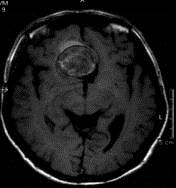

问题 病历摘要:??患者男性,56岁,因右侧视力下降伴视野缺损2个月来院就诊,诉头痛,无明显头晕,无视物重影,无恶心呕吐,无肢体抽搐,无肢体乏力,胃纳佳,大小便正常,既往史无特殊,入院检查:神志清楚,言语清楚,体毛分布正常,左侧视力4.6,右侧视力4.0,粗侧右颞侧视野缺损,左侧正常,颈软,四肢肌张力正常,肌力正常,病理征(-)。 大小为多少的动脉瘤称之为巨型动脉瘤?提示:该患者行全脑血管造影,诊断前交通巨型动脉瘤并部分血栓形成。